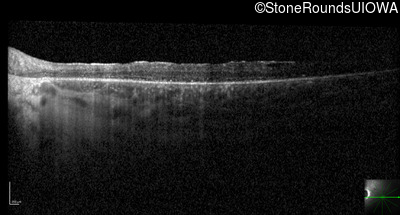

Optical Coherence Tomography - Right - 20/50

Exemplar / OCT Stack

OCT Stack